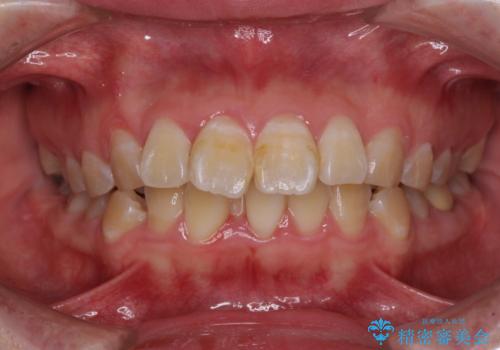

【インビザライン】マウスピース矯正希望。

担当医 河口智英